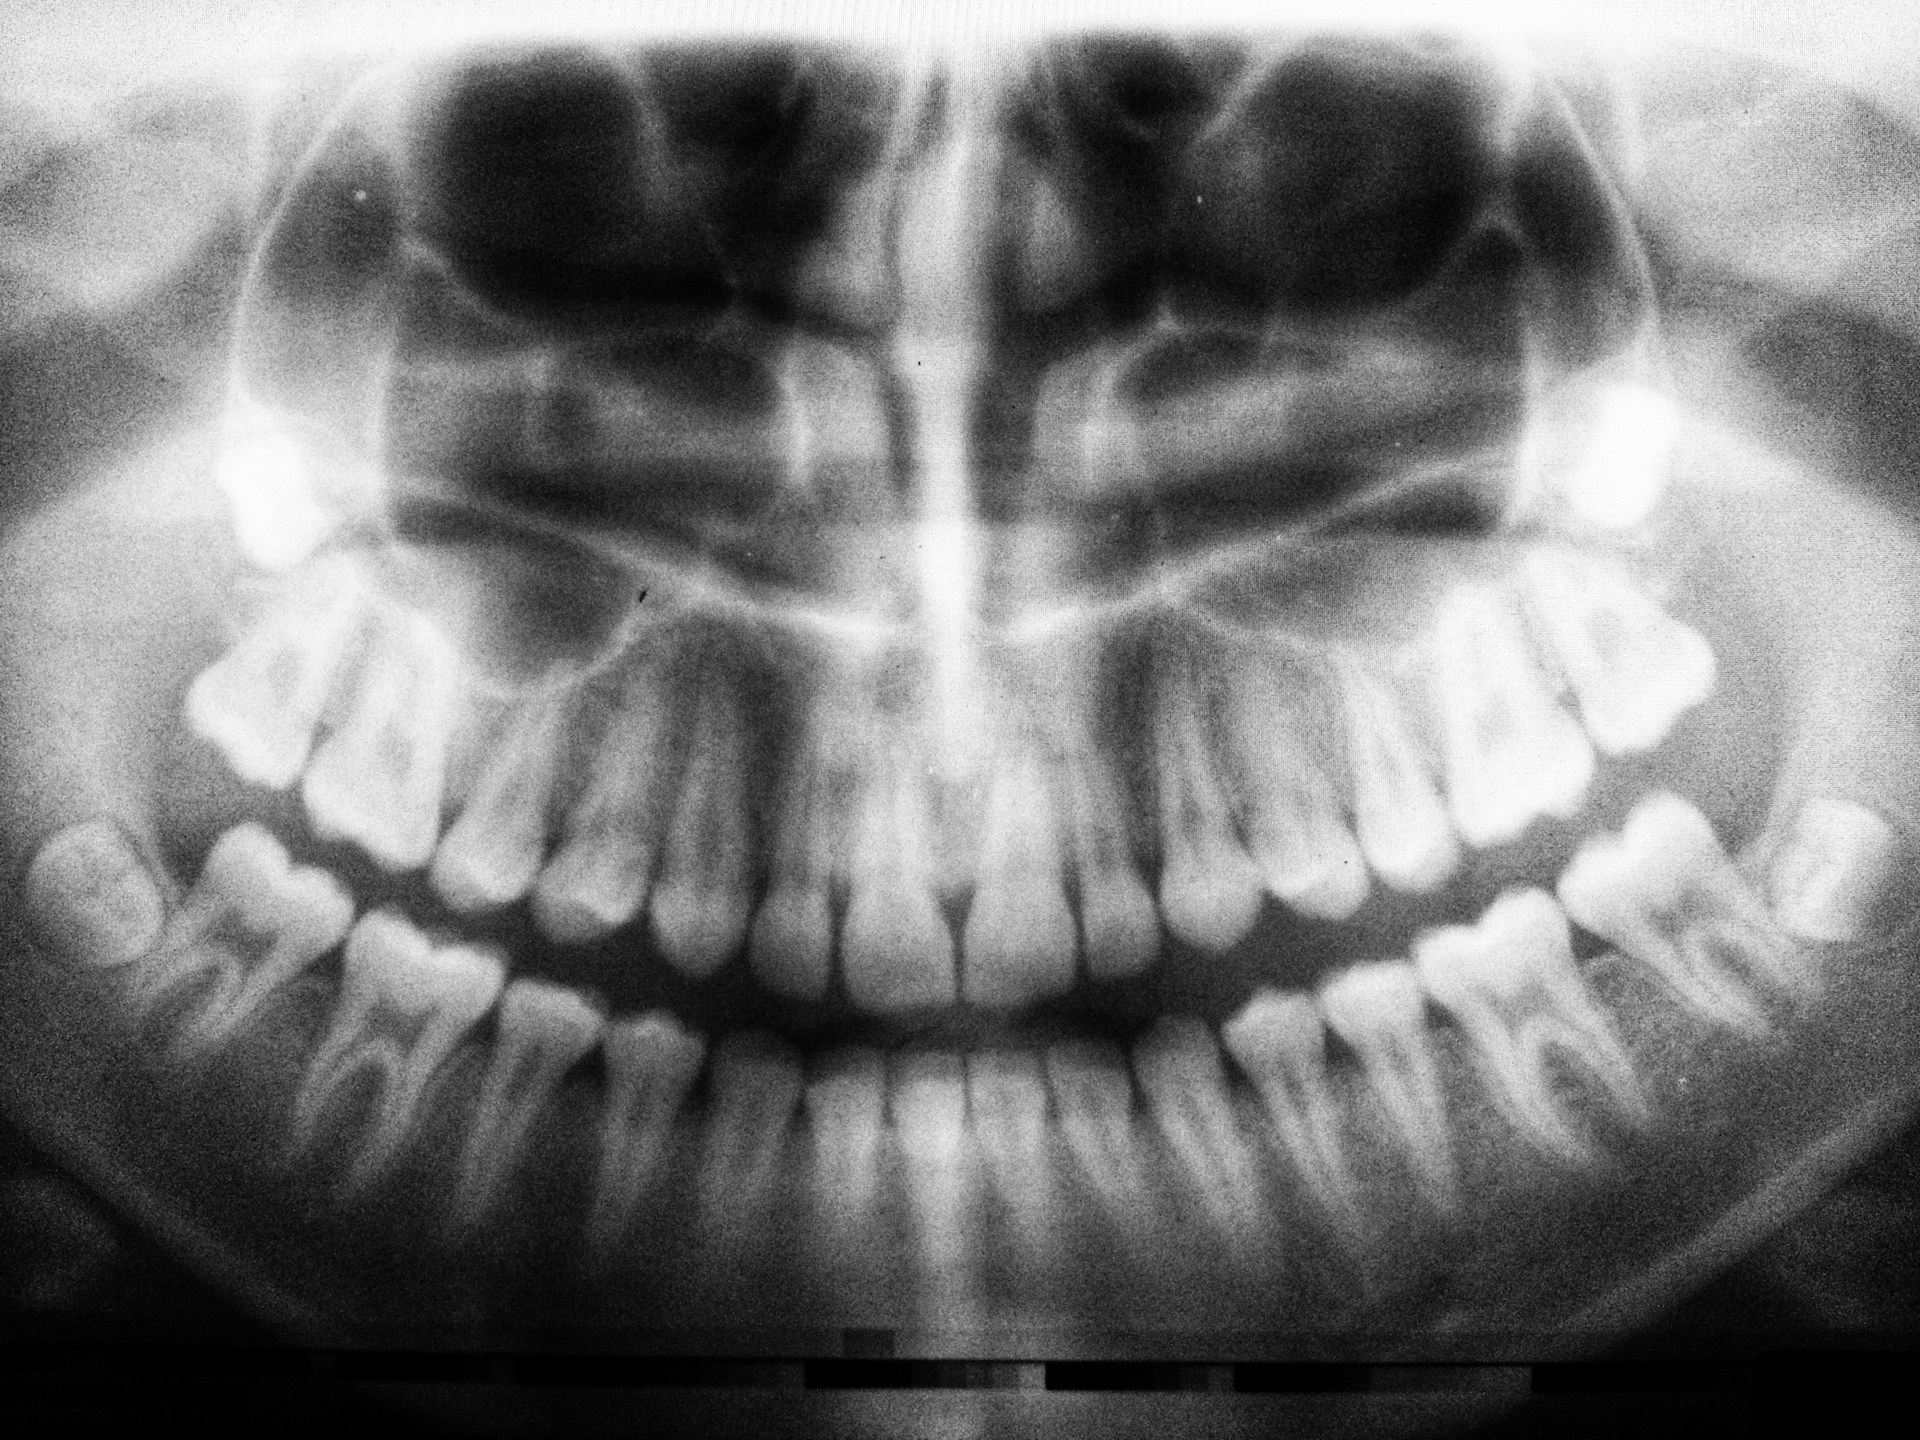

3D CBCT Imaging

In-house low-dose imaging for diagnostics & surgical planning.

Implants, wisdom teeth evaluation, nerve & sinus mapping.